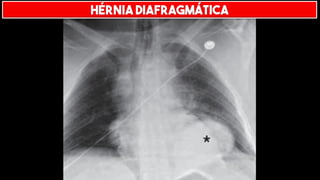

HÉRNIA DIAFRAGMÁTICA